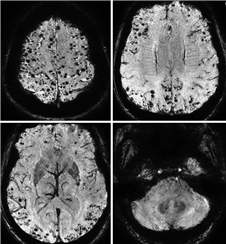

CAA是自发性脑出血的主要原因之一,特别是在高龄患者中[25],除了脑出血,CAA导致的出血性改变更多以脑微出血的形式出现。CAA相关的脑出血或微出血位于脑叶表浅部位,倾向于累及后部颞叶和枕叶,与Aβ沉积的部位选择性一致[6],在脑微出血数量较多的患者中,病灶有在同一脑叶聚集的趋势(图1)[23]。而高血压性脑出血和微出血主要累及深部灰质和脑干,脑叶出血和微出血也是生前诊断CAA的主要线索[6]。

明显的脑微出血偶尔可在T2WI上看到(图2),但脑微出血的识别更多地依赖MRI梯度回波序列(gradient echo, GRE)或磁敏感加权序列(susceptibility weighted imaging, SWI)。微小血管病变导致血液外渗,在GRE或SWI序列上表现为2~5 mm大小的圆形低信号区(图1,3)。钙化、离子沉积、海绵状血管瘤等与脑微出血表现类似,应注意鉴别[28]。